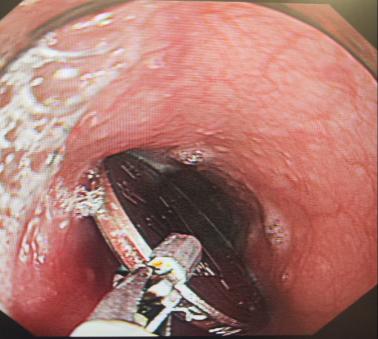

第二步:立即就醫(yī)內(nèi)鏡中心是首選??捎秒娮游哥R直觀地發(fā)現(xiàn)并取出食道的異物。

尖銳異物: 魚刺、雞骨頭、假牙等

圓形異物: 硬幣、紐扣電池、玩具零件(常見于兒童)

團(tuán)塊異物: 大塊的肉、果核、糯米團(tuán)等